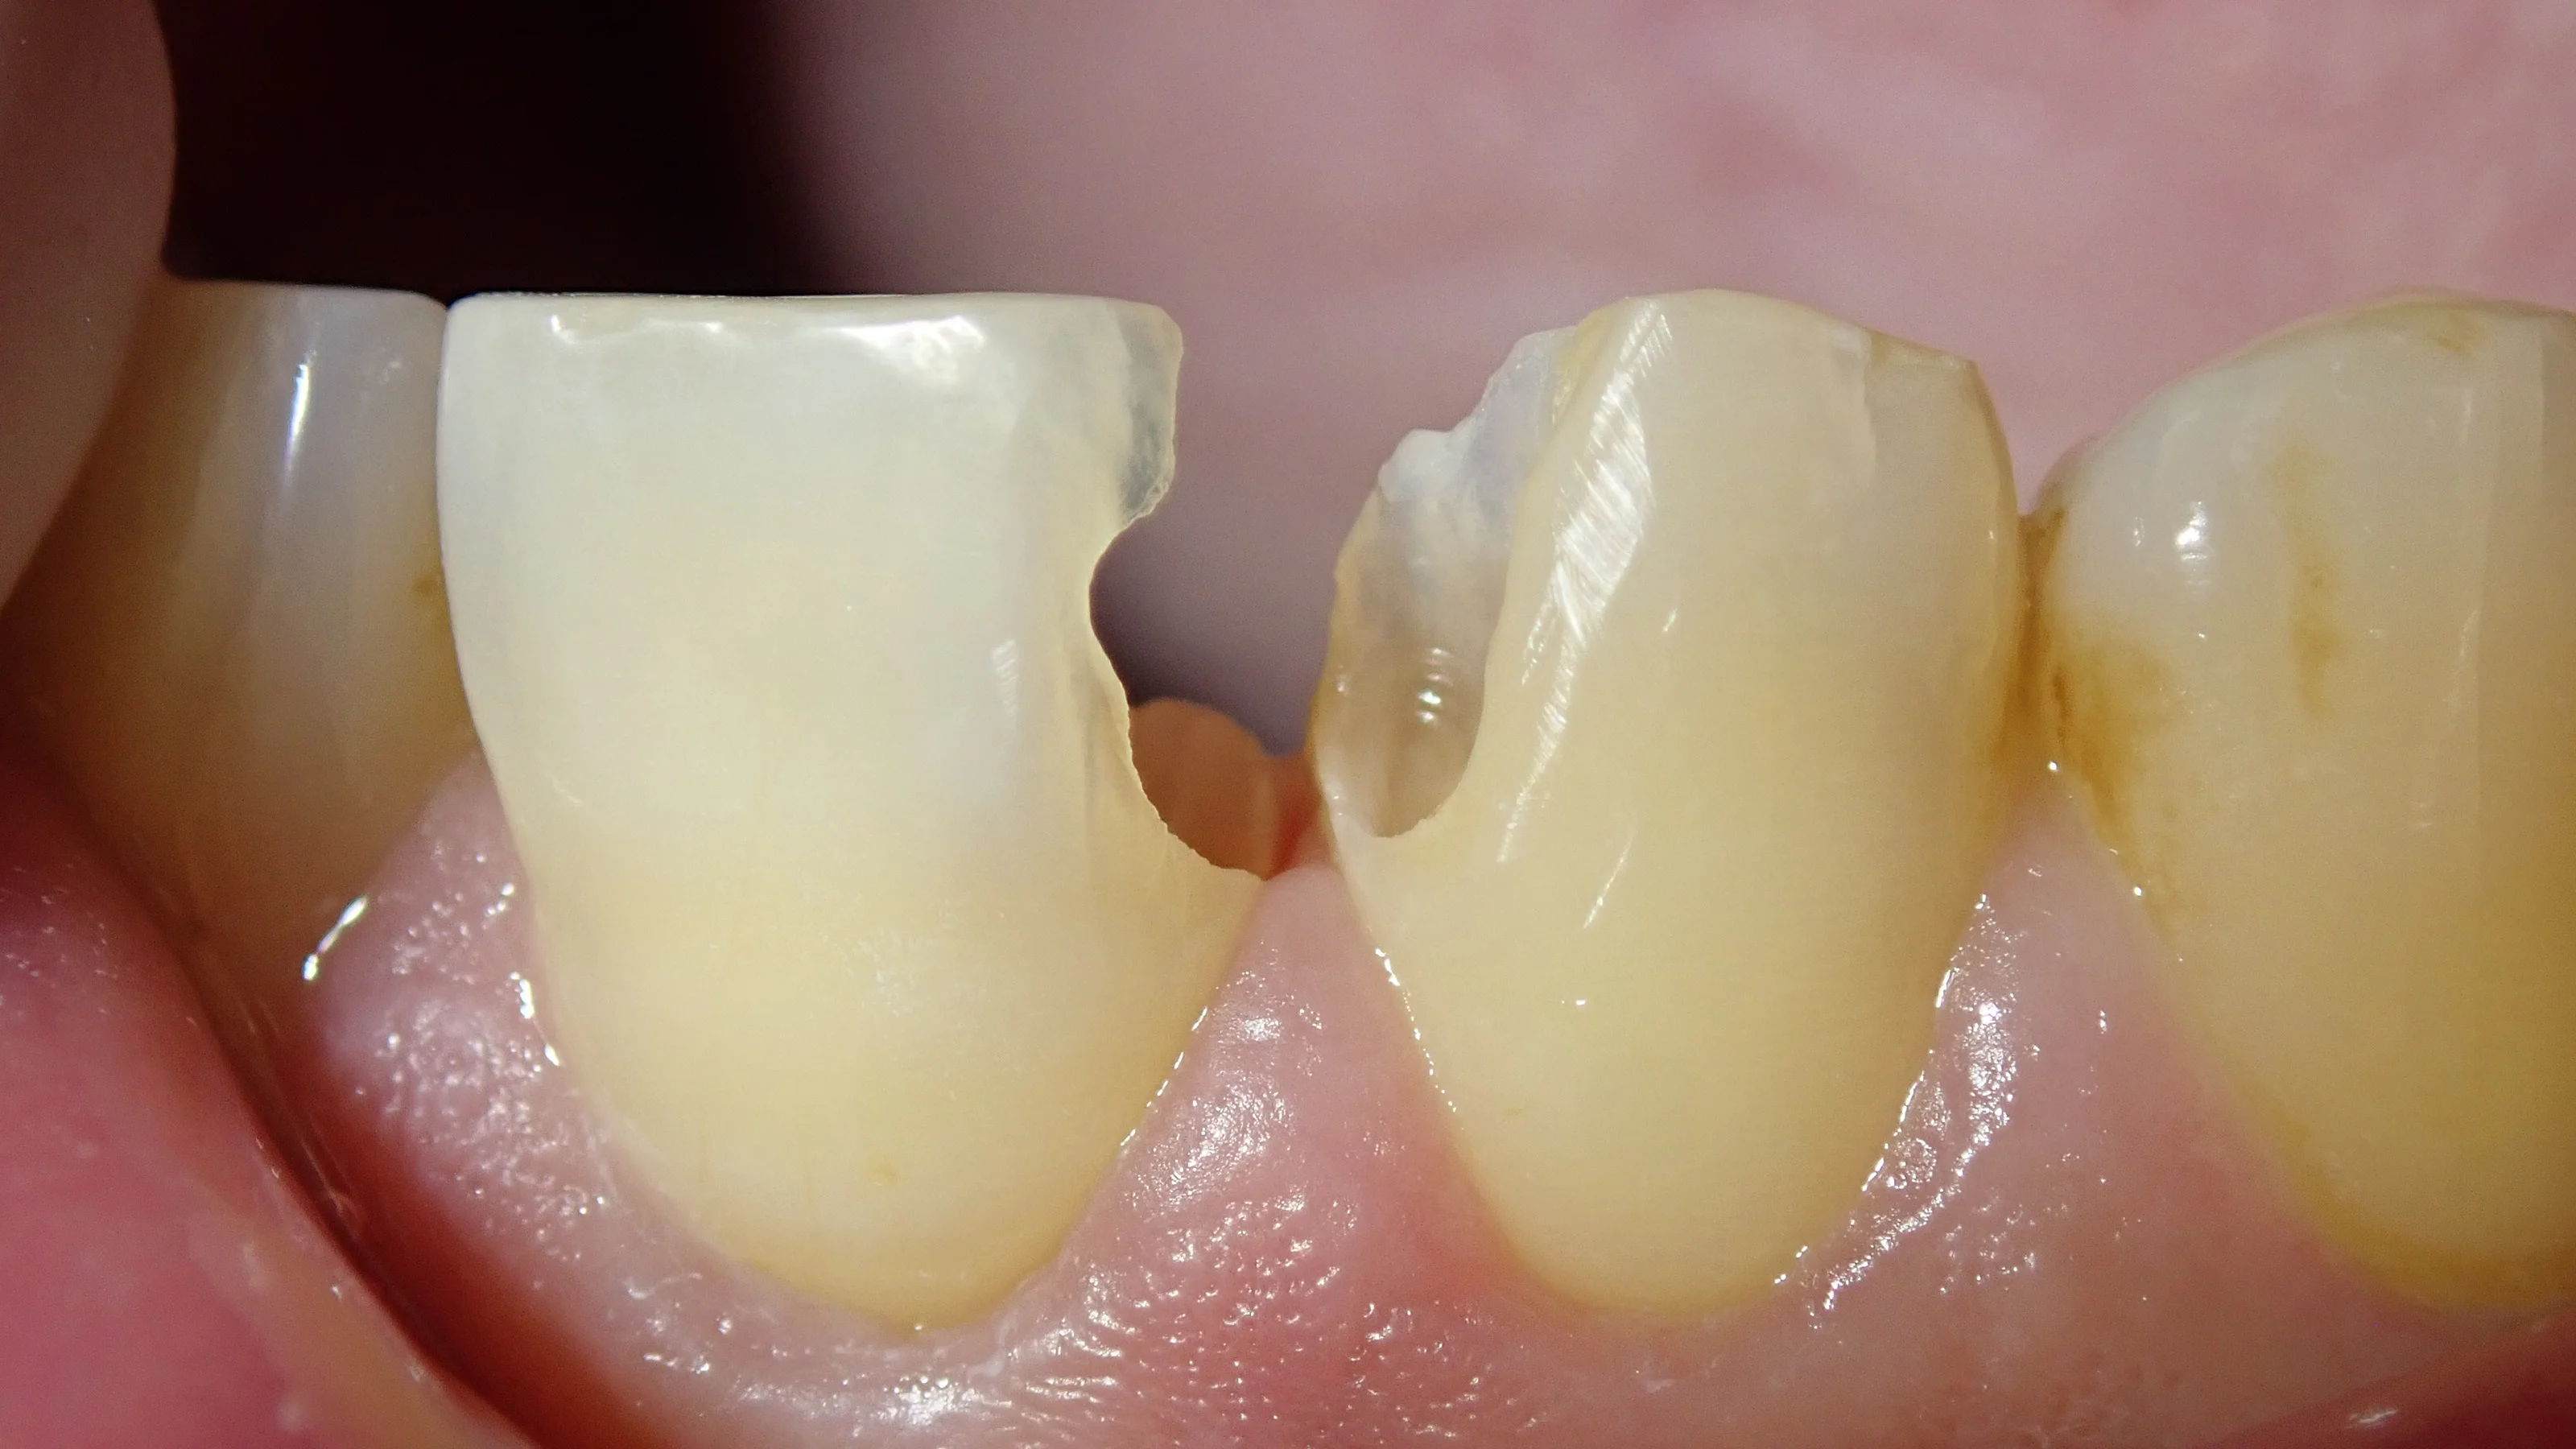

手前側の古い詰め物を除去したのがこちらです。

表から見た写真と

裏から見た写真です

裏から見ると内面がくろーくなってるのが分かりやすいですね。